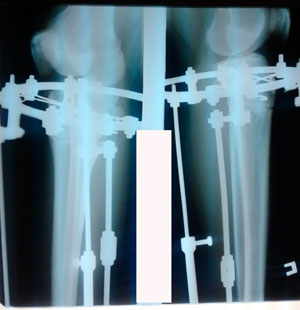

Исходник - 32 года.

Дата операции - 19.03.2020

image-19-03-20-12-29-2.jpg

image-19-03-20-12-29-1.jpg